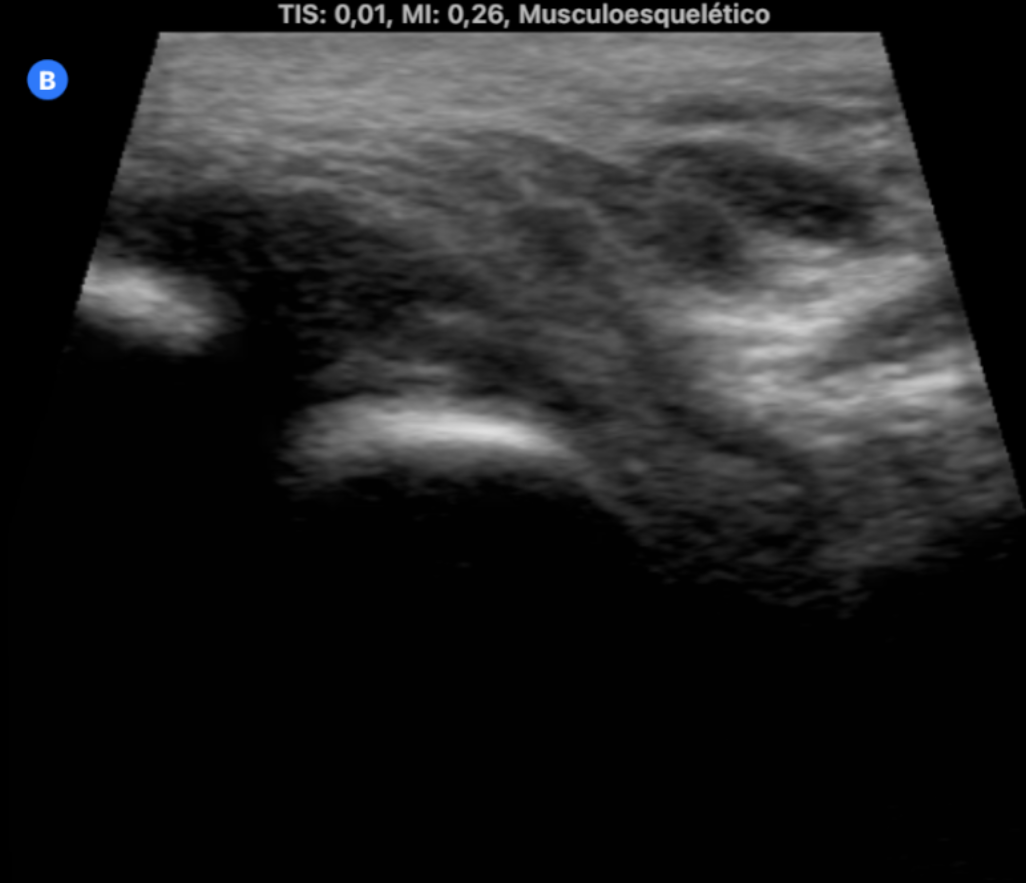

La medicina de familia no tiene horarios ni fronteras. Durante el último año, hemos incorporado el ecógrafo ultraportátil a nuestra vida diaria no como un recurso improvisado, sino como una herramienta integrada en nuestra práctica diaria capaz de dar respuesta inmediata a demandas clínicas surgidas en el entorno comunitario. En este contexto, han surgido situaciones en las que la ecografía ha sido determinante: diagnóstico de neumonías en domicilio, confirmación de roturas fibrilares tras actividad deportiva, fractura costal, valoración de hematomas y complicaciones postquirúrgicas, e incluso la identificación de una enfermedad pulmonar intersticial. Todo ello fuera del centro de salud, sin acceso a historia clínica ni a pruebas complementarias, únicamente con la sonda, la experiencia clínica… y una gran responsabilidad emocional. Estas situaciones generan un desafío distinto: no hay anonimato, y la confianza.

La ecografía ultraportátil amplía la capacidad resolutiva del médico de familia más allá de la consulta. Con herramientas sencillas y bien utilizadas, la Atención Primaria puede acercarse aún más a la población, ofrecer respuestas rápidas y mantener su esencia profundamente humana.

Cualquier médico de familia con formación básica en ecografía y acceso a un ecógrafo portátil puede implementar esta práctica. Especialmente útil en zonas rurales, en atención domiciliaria o en situaciones de difícil acceso al sistema. Reduce derivaciones innecesarias y mejora el acceso al diagnóstico precoz.